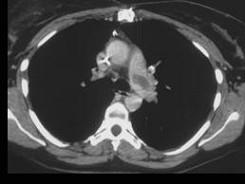

问题 女,51岁,心脏手术后,突感胸痛,结合CT图像,最可能的诊断是 ( )

选项 A、肺癌 B、肺不张 C、支气管扩张 D、肺水肿 E、肺栓塞

答案 E